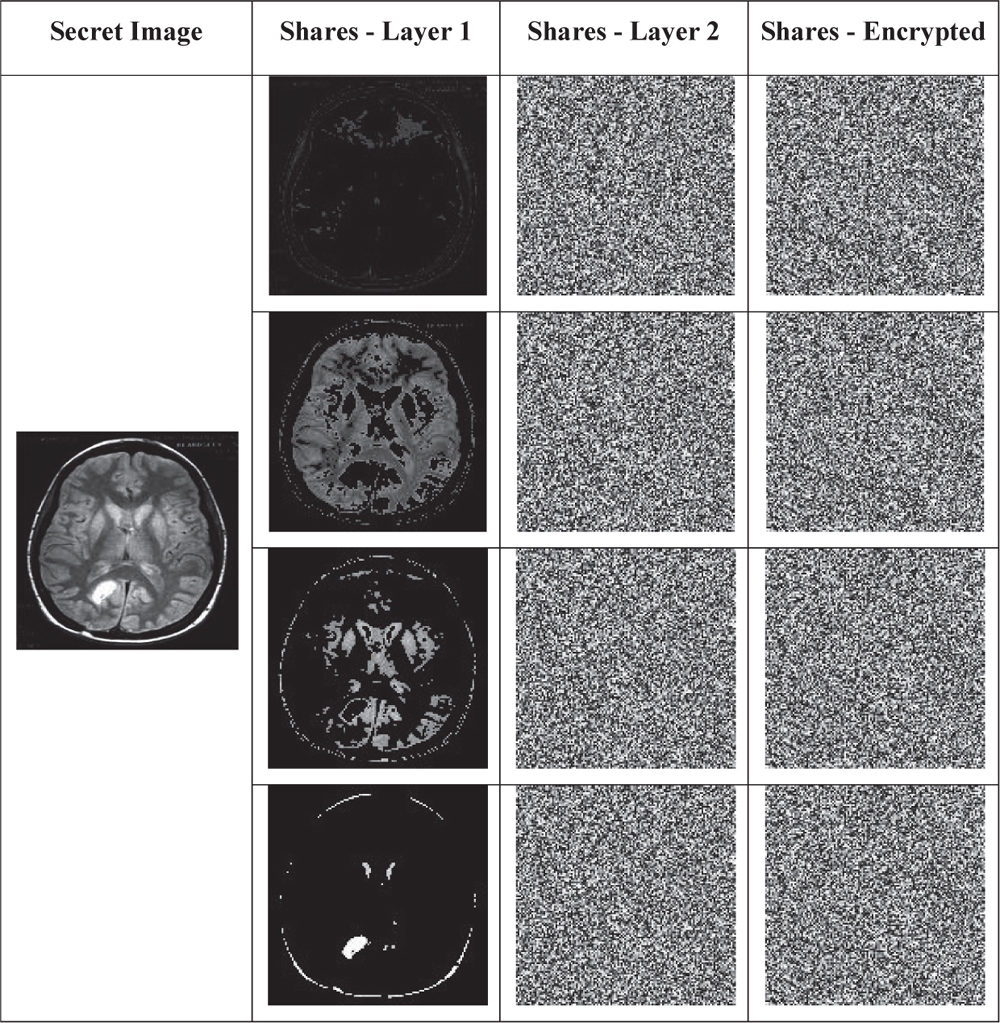

In this section, the intermediate results obtained for the proposed dual layer share creation method is provided. As the secret image is shared in two layers, the second column in Table 1 gives the results obtained with threshold based sharing. Moreover, the third column represents the shares obtained with proposed universal share based share creation method. Finally, the shares are encrypted using the OAFSO algorithm based stream cipher is shown in column 4 of Table 1.

Table 1 Secret image sharing results